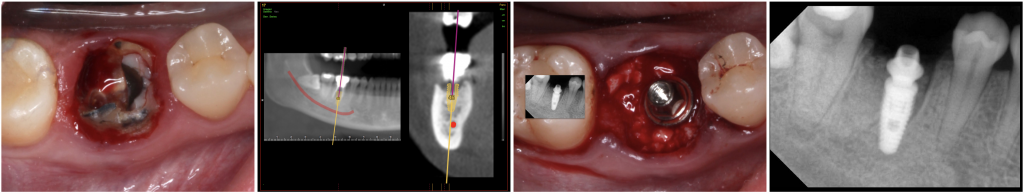

Fig. 1- Immediate Implant after extraction of a lower jaw first molar 46 (Neodent® Alvim), and placement of the definitive abutment (32 N.Cm).

The insertion torque range was 35 N to 60 N. The gap between the inner surface alveolar walls and the implant surface was filled with a grafting material (Instradent® Xenograft, cancellous 1.0-2.0mm, Nibec, South Korea) up to the implant platform. After implant insertion, a standard prosthetic abutments (2 CM abutments and 2 MiniCM abutments, Neodent) were connected (32 N) to the implants and the healing caps screwed (10 N) to the prosthetic abutments.